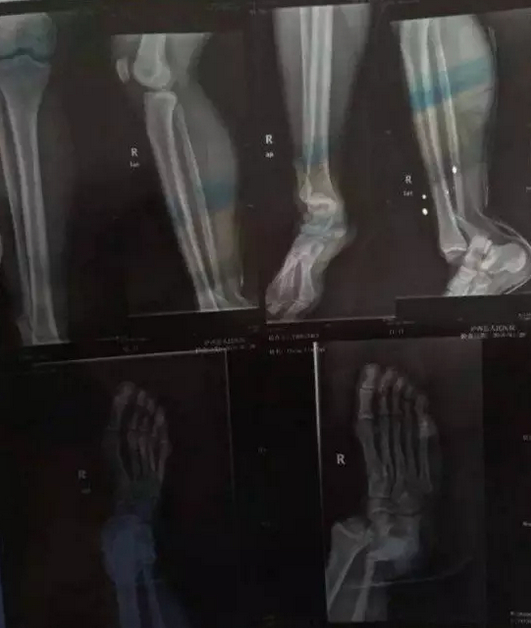

2016年的1月28日可能是一个张琳艳不愿再去回想的日子。当天,在云南进行的U16联赛中,代表恒大足校出战的张琳艳在一次拼抢中,被对方门将整个人压在了脚上。她的脚当场就变了形。

“最开始没哭。但是我看到我的脚变成那样,想,肯定要休息好几个月了,就哭了。结果还不止(休息)几个月。”在那时所有公开流传的照片中,张琳艳都是笑着面对镜头的。“当时不想让大家担心。”张琳艳说,被送往医院的路很陡,腿又太疼,实在忍不住才哭了。

医院诊断的结果是右脚腓骨骨折。三天后,张琳艳在四川省骨科医院接受了手术。手术很成功,但更煎熬的是随后的康复。整整四个月,张琳艳都没有下过地。医生告诉高红,张琳艳骨折的部位周围,连接的组织都遭到破坏,恐怕再也无法恢复到从前的水平了。